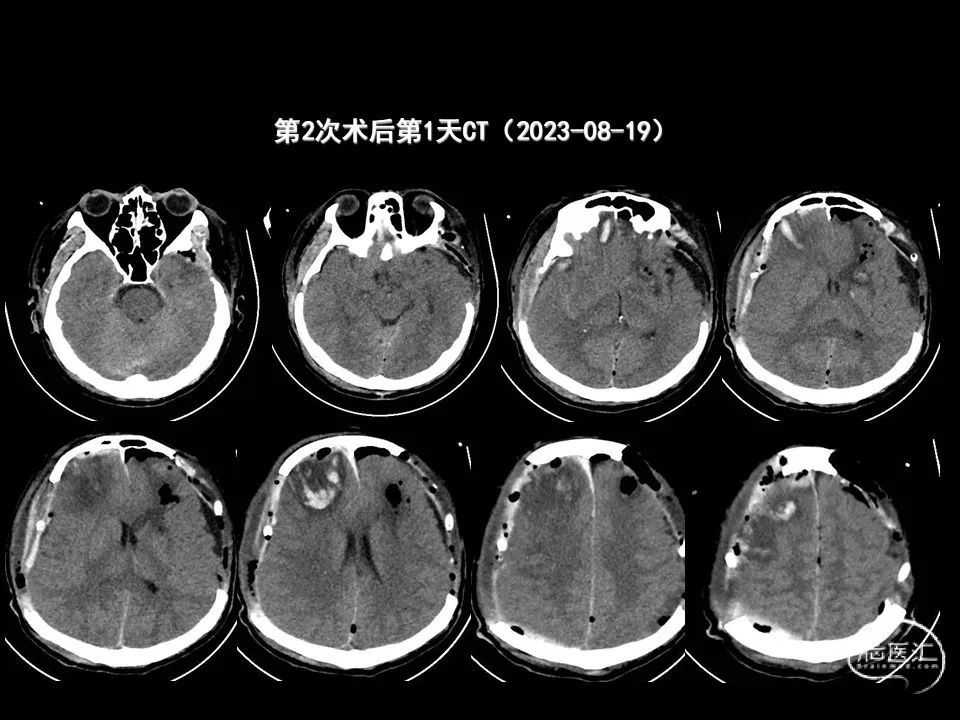

今天为大家分享的是《监测有道丨颅脑创伤-神经重症周刊》第338期,由海南省人民医院朱蔚林教授带来的:2例脑出血微创手术,欢迎阅读、分享。